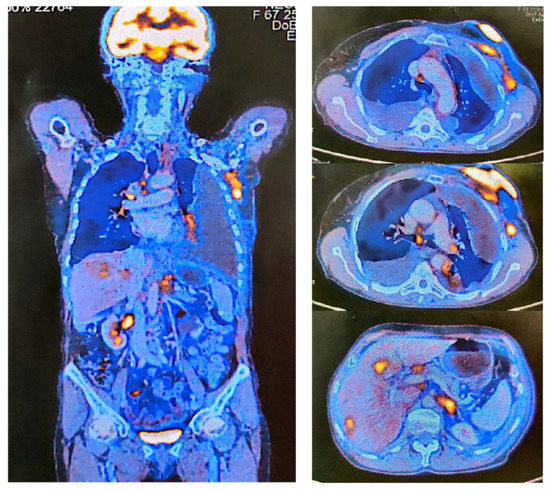

2. Case Report